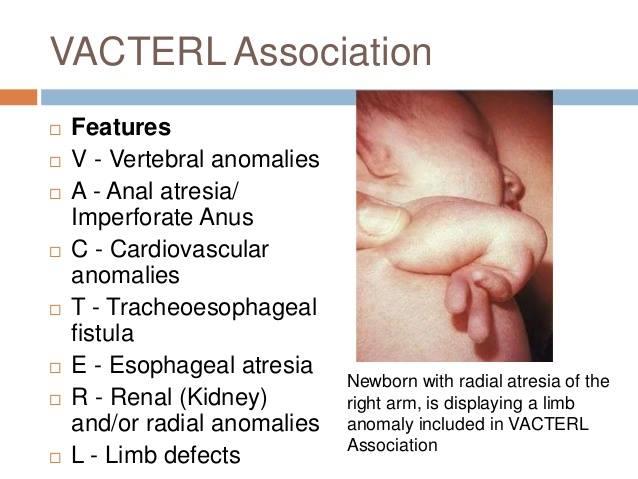

What is VACTERL?

Vertebral defects

Anal atresia

Cardiac defects

TracheoEsophageal atresia

Renal anomalies

Limb anomolies

vacterl

Esophageal atresia

How many anomalies need to be present to be considered VACTERL?

3